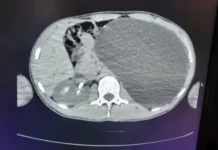

Врачи продемонстрировали модель повреждения и объяснили механизмы его возникновения. "Трещина – внезапный разрыв слизистой анального канала, – пояснил эксперт. – На начальной стадии без фиброзных изменений консервативное лечение эффективно. Кровь при дефекации или непреходящая боль – сигналы для немедленного обращения к специалисту".